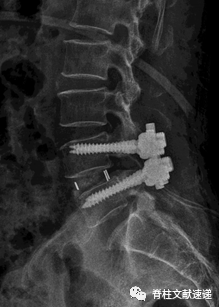

该文献旨在探索出TLIF术后cage移位(CM)和cage退回(CR即cage移位至椎管内)的危险因素,对784位(共881个节段)行TLIF术的患者进行随访与观察,术后共有56个节段发生了cage移位CM(6.4%),其中17个节段(30.4%)被认定为cage退回CR,17.9%的CM患者和0%的CR患者cage位置靠前,而82.1%的CM患者和100%的CR患者cage位置靠后(OR=6.45,P=0.04)。

因此作者认为cage放置位置靠后,是cage移位(CM)和cage退回发生的重要危险因素,此外作者还发现骨质疏松症、术中终板的损伤、梨形的椎间盘和术中只使用一个cage也与CR和CM的发生相关。

图注:上图为术后即刻X线片,下图为术后3个月X线片,可以看出该患者发生了术后cage移位(CM)。